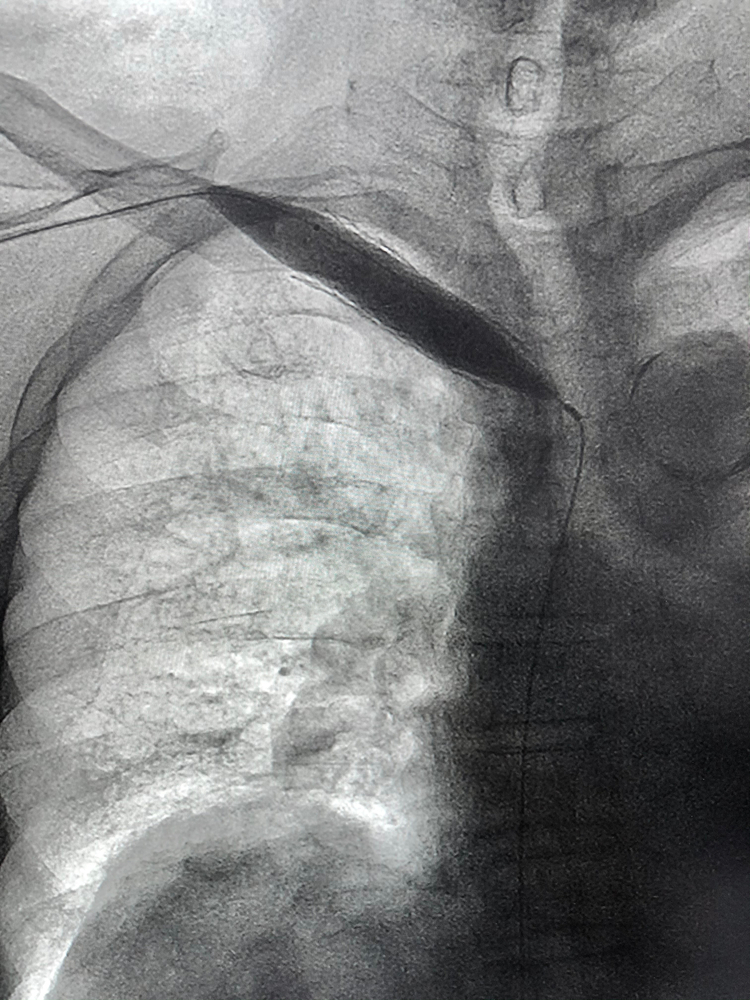

Η ενδαγγειακά υποβοηθούμενη ωρίμανση αποτελεί μια ελάχιστα επεμβατική τεχνική που εφαρμόζεται σε φίστουλες που δεν παρουσιάζουν επαρκή ανάπτυξη. Μέσω αυτής της διαδικασίας, χρησιμοποιούνται διαστολές με μπαλόνι (αγγειοπλαστική), τοποθέτηση ενδοπροθέσεων (stents) ή άλλες συνδυαστικές τεχνικές για να ενισχύσουν τη ροή του αίματος και να διευκολύνουν την ωρίμανση της φίστουλας.

Η διαδικασία αυτή πραγματοποιείται ενδαγγειακά, δηλαδή μέσω ενός μικρού καθετήρα που εισάγεται στα αγγεία, χωρίς να απαιτείται χειρουργική τομή. Έχει αποδειχθεί ότι αυξάνει την πιθανότητα επιτυχούς ωρίμανσης, επιτρέποντας σε περισσότερους ασθενείς να χρησιμοποιήσουν τη φίστουλα για αιμοκάθαρση.

Αγγειοπλαστική με μπαλόνι

Η πιο συχνά χρησιμοποιούμενη μέθοδος περιλαμβάνει τη διάνοιξη των στενωμένων αγγείων με τη χρήση ειδικών καθετήρων με μπαλόνι, είτε απλών, είτε υψηλών πιέσεων. Το μπαλόνι διαστέλλεται μέσα στη φλέβα, διευρύνοντας τη διάμετρό της και επιτρέποντας τη βελτίωση της ροής του αίματος.